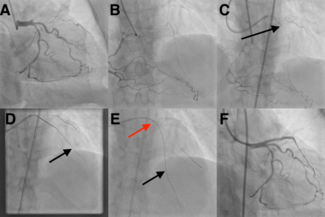

Eugene B. Wu, MD, DM; Ken W. K. Chi, MD

The authors report the Extraplaque Blood Withdrawal stenting technique to treat chronic total occlusion percutaneous coronary intervention-induced extraplaque hematoma.